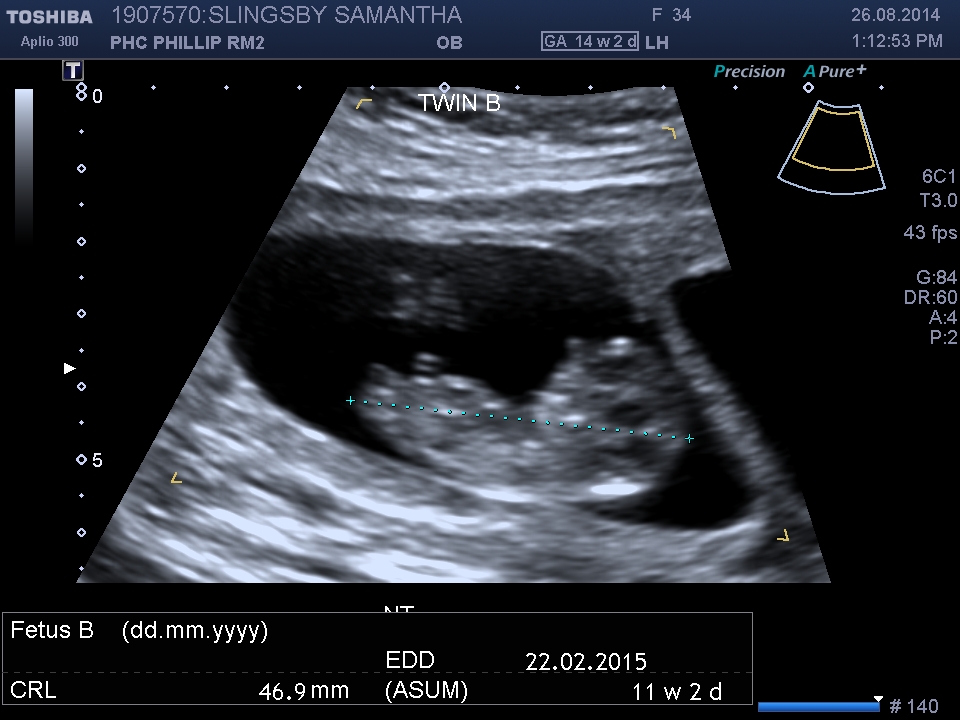

It's 11weeks + 2.